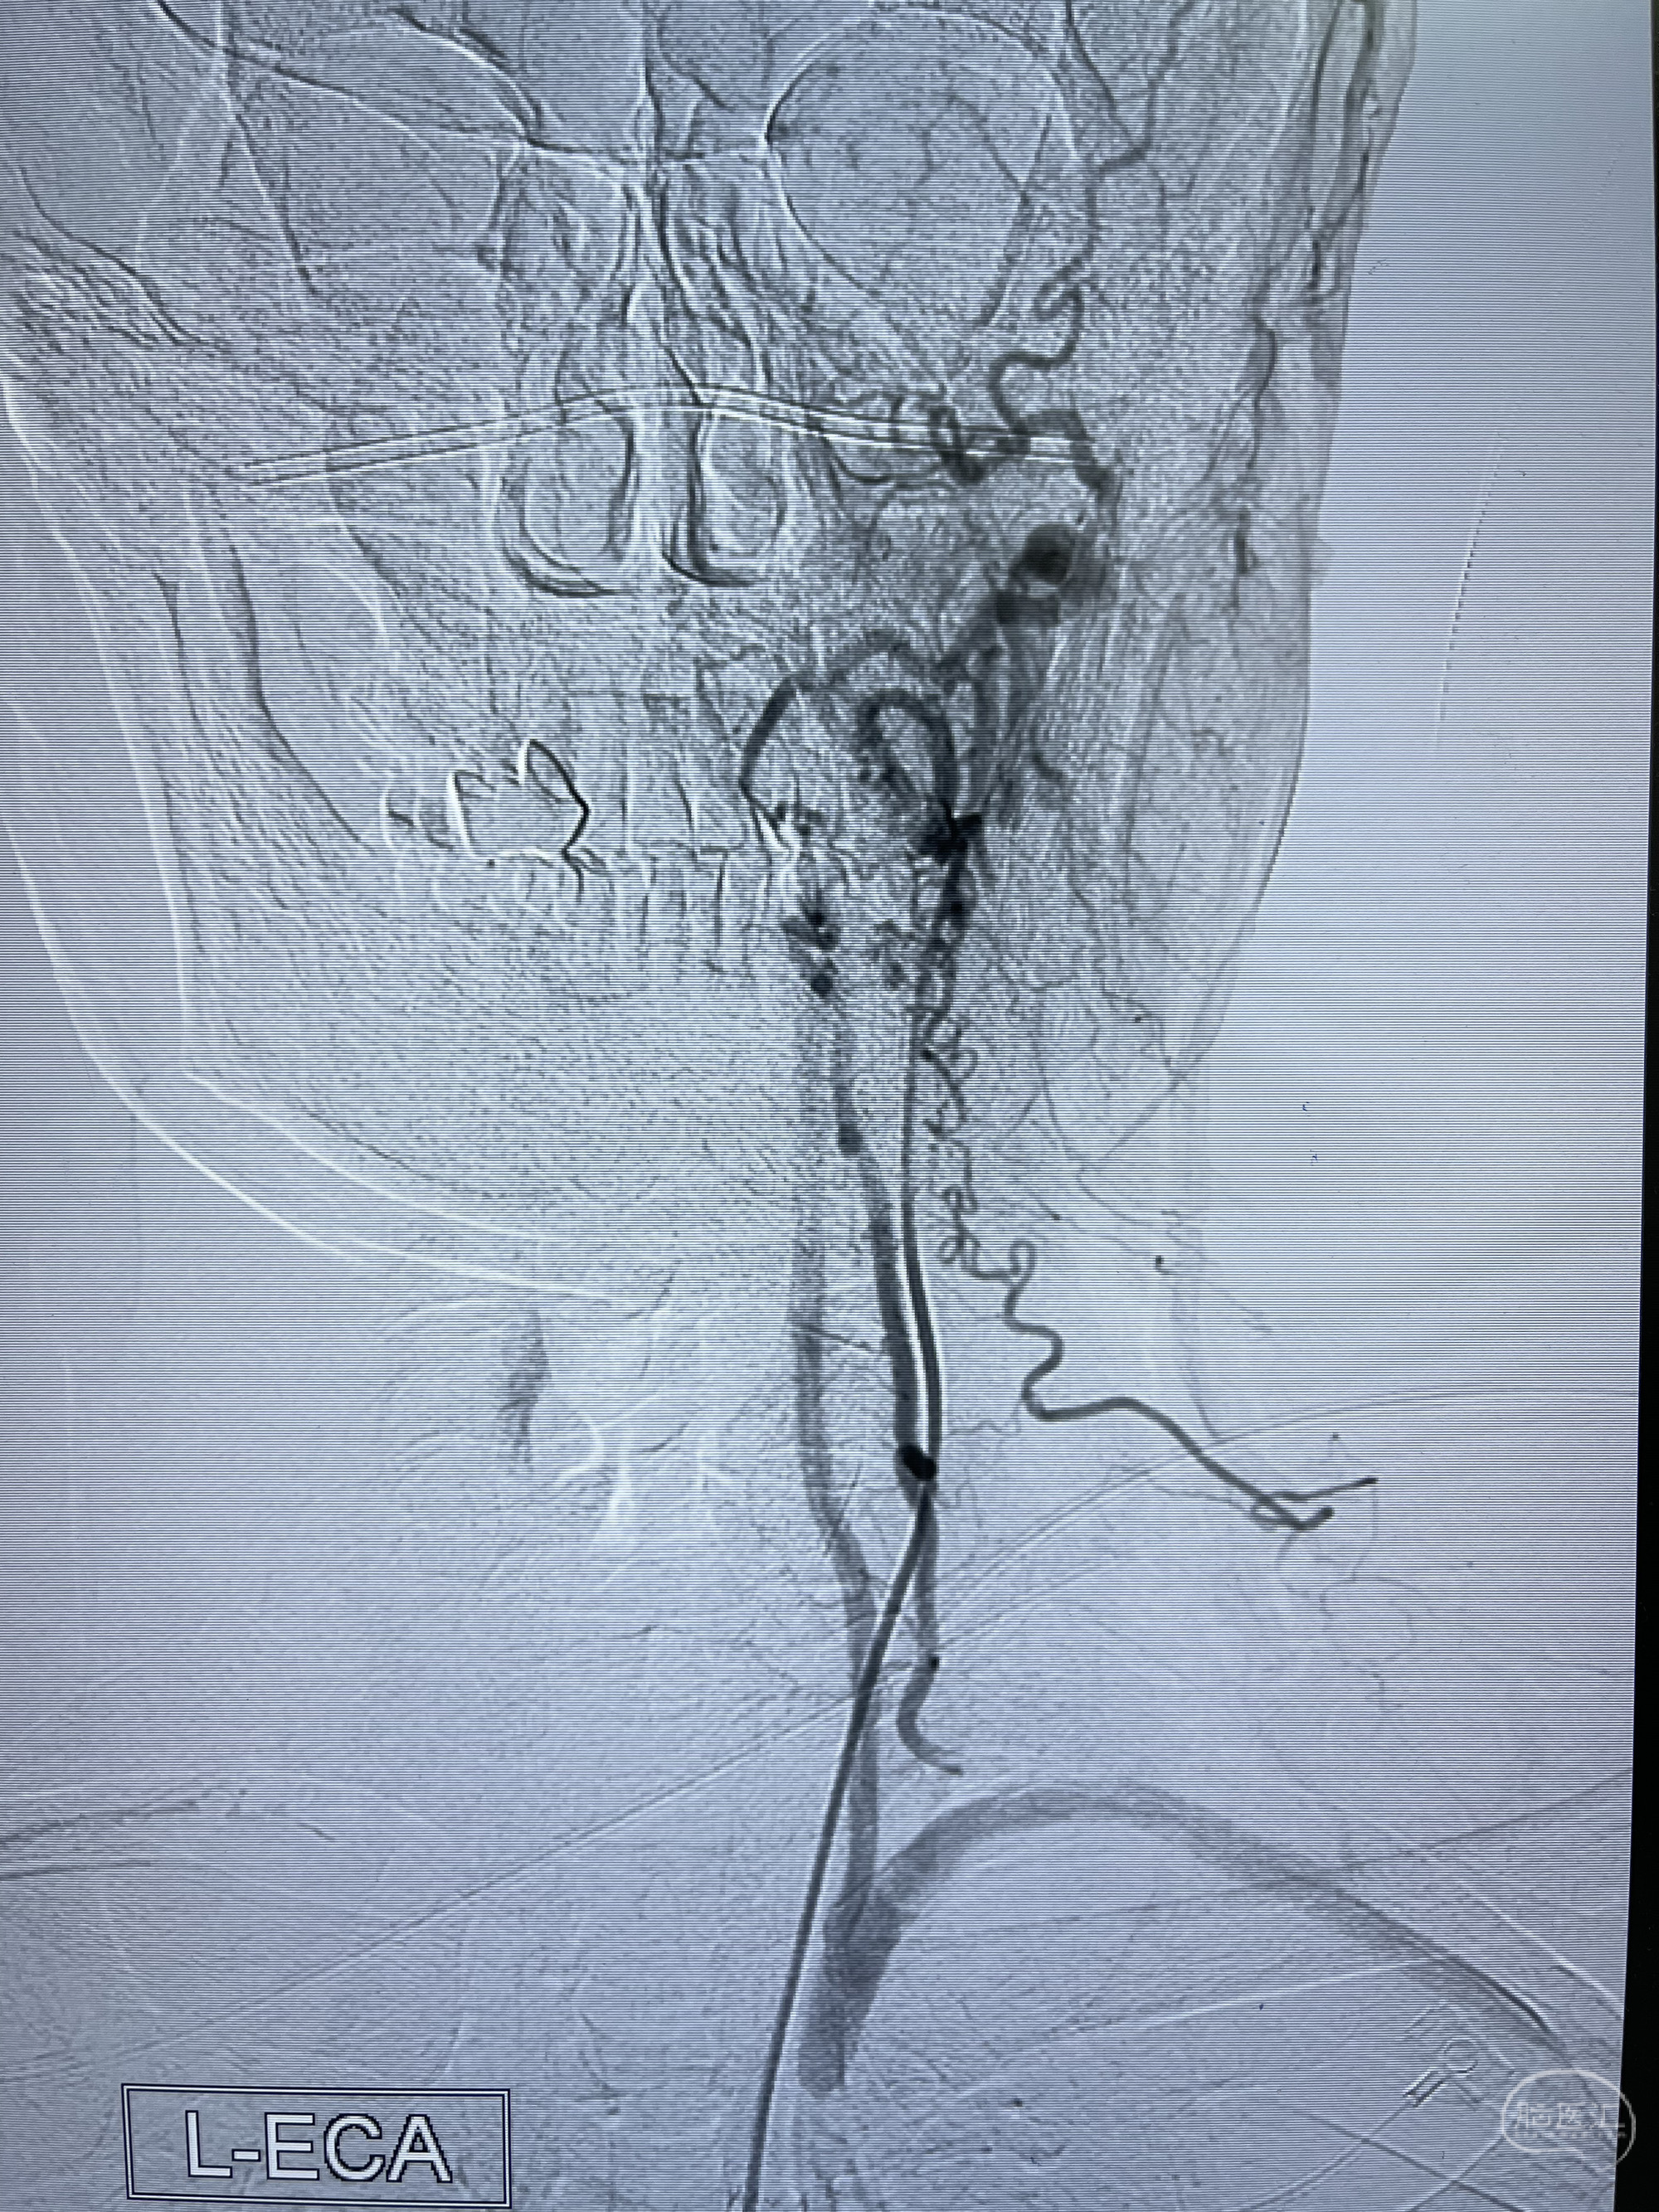

4.右侧颈外动脉可见经由右侧脑膜中动脉吻合显影右侧眼动脉及颈内动脉

6.左侧颈外动脉可见吻合显影至左侧椎动脉并逆行供血至左侧腋动脉

左侧颈外动脉经脑膜支吻合至左侧椎动脉—左侧锁骨下动脉—左侧上肢